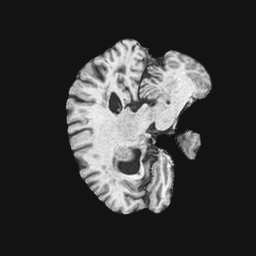

Exp. 2: Fetal brain data is used to test the robustness of our approach under real conditions. Fetuses younger than 30 weeks very often move a lot during examination. Fast MRI sequences allow artifact free acquisition of individual slices but motion between slices corrupts consistent 3D information. Fig. 3 shows that our method is able to accurately predict Ti^^subscript𝑇𝑖\hat{T_{i}} also under these conditions. For this experiment we use ωisubscript𝜔𝑖{\omega_{i}} from three orthogonally overlapping stacks of ssFSE slices covering the fetal brain with approximately 20-30 slices each. We are ignoring the stack transformations relative to the scanner and treat each ωisubscript𝜔𝑖{\omega_{i}} individually. For ΩtrainsubscriptΩ𝑡𝑟𝑎𝑖𝑛\Omega_{train}, 28 clinically approved motion compensated brain reconstructions are resampled into a 150×150×150150150150150\times 150\times 150 volume with 1mm×1mm×1mm1𝑚𝑚1𝑚𝑚1𝑚𝑚1mm\times 1mm\times 1mm spacing. A density of 500 unique sampling normals has been chosen via the Fibonacci sphere sampling method with 25 sampling planes evenly spaced between -25 to +25 on the Z-axis. This gives a plane spacing of 2mm, sampling only the middle portion of the fetal brain. Training took approximately 10hrs for 30 epochs. Prediction, i.e., the forward pass through the network, takes approx. 12 ms/slice.

Figure 3: Comparison of a single slice from a heavily motion corrupted stack of ssFSE T2 weighted fetal brain MRI (a); axial multi planar reconstruction of one sagittal input stack (b); a slice at approximately the same position through a randomly selected training volume (c); failed reconstruction attempt using standard SVR based on three orthogonal stacks of 2D slices (d) (the fetus moved heavily between the acquisition of the individual stacks); reconstruction based on SVRNet Ti^^subscript𝑇𝑖\hat{T_{i}} regression (e); SVR initialised with SVRNet transformations after eight iterations of SVR (f). Note that (e) and (f) are reconstructed directly in canonical atlas co-ordinates.